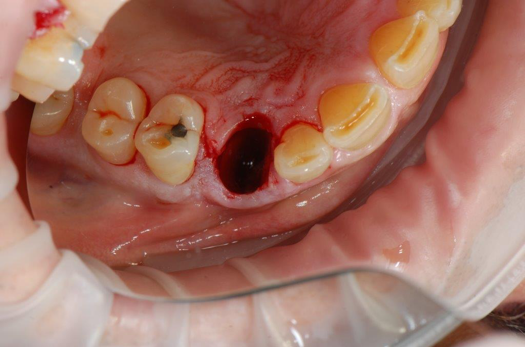

Fig 19. Atraumatic extraction.

Figure 19

Fig 20. Immediately after extraction and placement.

Figure 20

Occasionally dentists are presented with extreme challenges with long-term restorations and replacing missing teeth. Dentists must evaluate the patient's condition, develop optimum long-term oral health, and attempt to meet the patient's expectations. Figure 18 showed a class III malocclusion with deep bite, multiple abfractions, and less-than-ideal occlusal plane, but the patient wanted to replace his maxillary right canine only. A discussion with the patient regarding occlusal disharmonies and comprehensive recommendations for full-mouth rehabilitation revealed that the patient had a limited budget for dental care. The patient understood the ramifications of his comprehensive dental needs not being affordable. Decisions were made to atraumatically remove the maxillary right canine (Figure 19) and immediately place a ceramic dental implant (Figure 20). Polytetrafluoroethylene (PTFE) 4-0 sutures were placed to help support soft tissues, and then a full-arch Essix-style retainer with a flowable composite facial veneer was used to provide some esthetics during the patient's healing phase (Figure 21). The implant and the retainer were not to be in contactthe retainer may occlude with the opposing dentition and also be passive in relation to the ceramic implant.